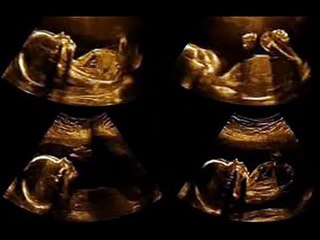

PREGNANCY INFORMATION WEEK 28 II गर्भावस्था का 28वां हफ्ता और ढेरो खुशियाँ II br br Baby is getting ready to meet you, so be sure you’re ready to meet her. Make a list of items you still need to acquire for your nursery. Start considering what you’ll pack to take to hospital. It’s not too early to get the bag packed. br Welcome to the third trimester! Moms-to-be who are at 28 weeks and beyond are known for their lack of sleep. Remember if you find yourself up in the middle of the night, do something relaxing. This is not the time to vacuum the house from top to bottom -- even though you might feel the urge to do that at some point. Read a book, drink chamomile tea, listen to soothing music. Then try to get back to bed and get some rest! Being in the third trimester also means much of your and baby’s anatomy are ready to go -- she's prepping for breathing, and your breasts already have colostrum, which is what baby will eat the first few days until your milk comes in. You’ll also start feeling more Braxton Hicks contractions as your body gets ready for labor. Baby will keep getting bigger -- and smarter -- after week 28, and other than that, she just needs a few more finishing touches. br br In this video our beautiful and talented anchor Parinita Rohrra is giving us information about 28th week of pregnancy. br br You can also view our other maternity, pregnancy related informative videos , health benefits & home made beauty tips videos to get solution to your all health & beauty related problems naturally. br br SUBSCRIBE OUR CHANNEL FOR REGULAR UPDATES: br br Like us on Facebook: br br br Follow us on Twitter: br br br You can also share this video on Whatsapp too. br br Please visit our other channels as they are fully accomplished to meet your queries in relevance with all types of information. These videos will be about beauty tips, health tips, cooking tips, pregnancy information, comedy and many more entertaining & informative stuff by our talented and experts anchors. br br Click on the link below to get lots of beauty tips by a famous Movie & TV actress Roma br br br br Many more beauty tips by a young, talented & beautiful TV actress Ms. Jyotika Sharma br br br br Click on the link below to get more than 400 home remedies to cure yourself and your near & dear ones lives naturally and without any side effects by Multi talented & expert anchor Mr. Piyush Shrivastava br br br br Click on the link below to have a stress free and healthy life style by the group of very talented, expertise & famous Yoga instructors. br br br br For all the bachelors out there, who lives alone without family. F3 is here to solve all your kitchen queries. Click on the link below to have more than 300 cooking recipes in various cuisines to meet your appetite level in a healthier manner by our very own talented Chef Mr. Piyush Shrivastava br br br br Click on the link below to have a solution to all your queries related to beauty and kitchen by very famous & beautiful TV & Movie actress Ms. Priyanka Saini br br br br br Click on the link below to get various types of delicious, tempting, quick to make cooking recipes that includes solutions for your all the cooking related queries from our multiple & multi talented anchors. br br br br click on the link below to have solution for all the queries & remarkable information related to your kids behavioural problems, beauty tips & lot of informative videos related to your internal and external health and many more. br br br br br Click on the link below and get entered into the lovely world of kids loaded with melodious rhymes & moral stories. br br br br Click on the link given below to get more delicious & mouth watering and instant recipes.